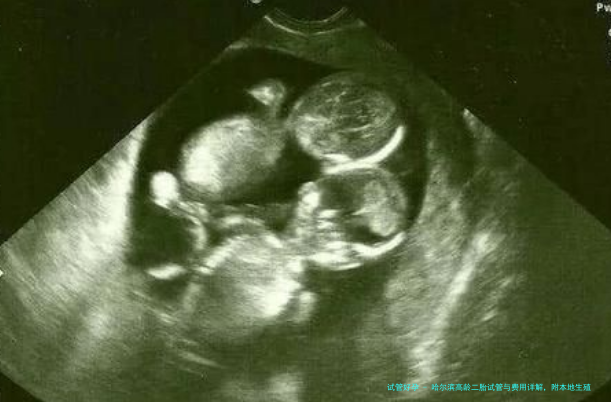

对于许多渴想通过人类辅助生殖技术实现二胎梦想的年长女性来讲,哈尔滨地区有哪些可靠的生殖医学中心?如何?费用又是怎样?这一些都是所有人关怀的问题。今日我们就来深入探讨一下,并结合内地使用的人的真实反馈,为众人提供一个清晰的参考。

高龄(通常指35岁以上)女性进行试管婴儿,面临着卵巢功能下降、卵子质量可能降低等挑战。选定一家技术过硬、经验丰富的生殖医学中心至关重要。这不只是简单的“排行”问题,越发需要要综合考虑医院的实验室技术、医生对高龄病例的个体化方案制定本事以及全程的关怀服务。